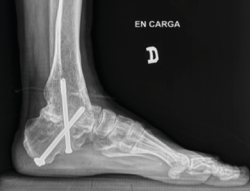

Figura 15. Control posquirúrgico tras la corrección de la pseudoartrosis en varo.

Utilidad de la impresión 3D: se decidió imprimir una guía 3D de corte como ayuda intraoperatoria. La guía permite la resección de la coalición de manera completa y reducir la necesidad de guía con fluoroscopia.

- Control posquirúrgico tras la corrección de la pseudoartrosis en varo (Figura 15).